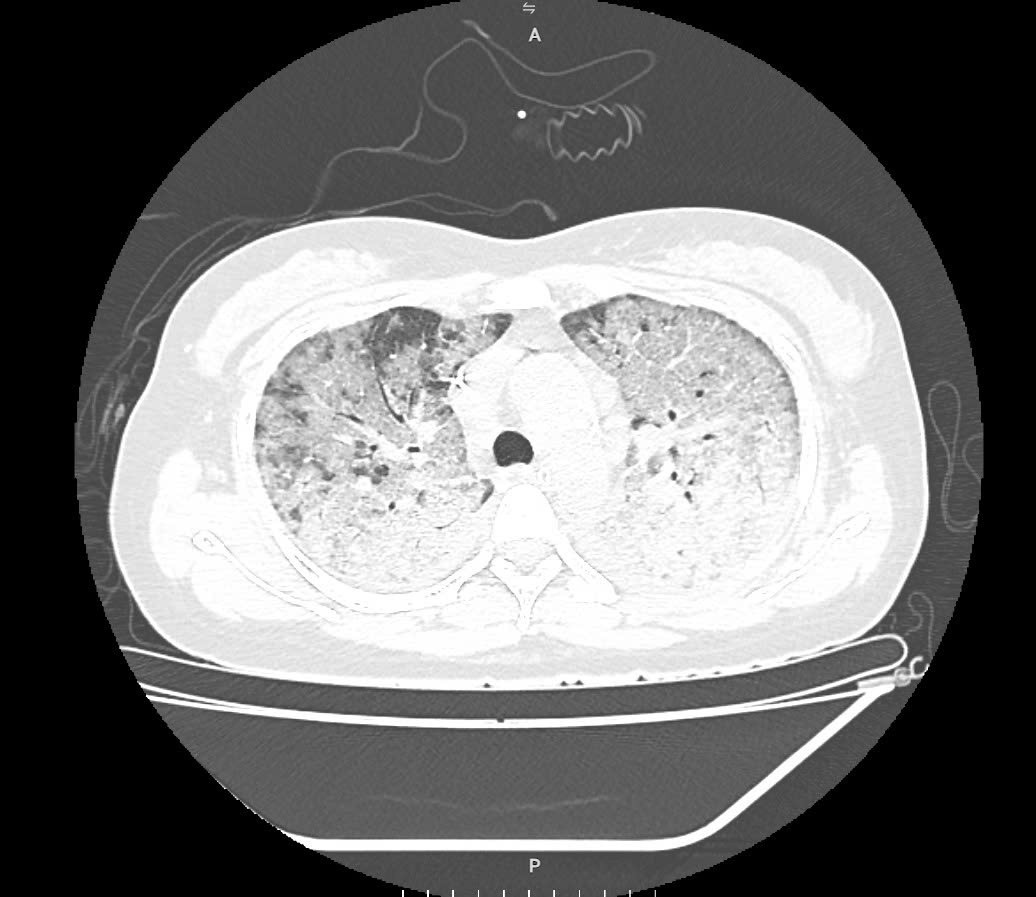

Hình ảnh phim phổi cho thấy tổn thương lan tỏa kín hai bên phổi, hình ảnh kính mờ điển hình của cúm tiến triển, nhanh chóng chuyển sang hội chứng suy hô hấp cấp (ARDS) – biến chứng nặng thường gặp ở nhóm bệnh nhân suy giảm miễn dịch.

cum-mua.jpg

Hình ảnh tổn thương phổi trên phim chụp của bệnh nhân - Ảnh BVCC